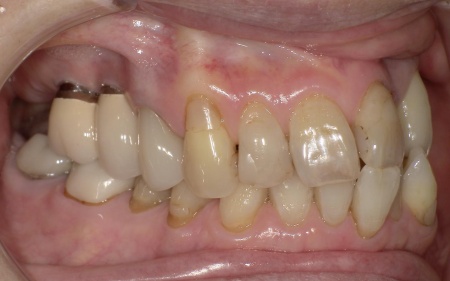

70代女性 歯根が折れた歯を抜いて金属バネを使用しない部分入れ歯で補った症例

「被せ物が装着されている左上奥歯で固いものを噛むと痛む」とご相談いただきました。

拝見したところ、左上の歯(第2小臼歯)が欠損しており、この部分を補うために、両隣の歯を土台として橋を渡すように連結した被せ物「ブリッジ」が装着されていました。

レントゲン撮影をして詳しく検査した結果、ブリッジを支えている左上の歯(第1小臼歯)は、歯根が割れていることが判明しました。

このまま放置すると、周囲の骨や歯茎に炎症が広がるおそれがあります。また、歯の状態から温存は困難だと判断しました。

以上のことから、歯根が折れた歯を抜いたうえで、欠損部位を補う治療が必要だと診断しました。

患者様は30年以上当院に通院されており、インプラント治療を行った経験があります。

ただ、最近転倒による骨折を経験されており、体力面の不安から外科処置を伴うインプラント治療は避けたいとのことでした。

併せて「健康な歯を削りたくない。また、笑ったときに金具が見えるのも避けたい」と希望されています。

以上のことから、患者様は③の部分入れ歯による治療を選択されました。

今回は審美性を考慮して、金属のバネではなく樹脂の留め具で固定する部分入れ歯「ノンクラスプデンチャー」を提案し、同意いただきました。

第1小臼歯に歯根破折を認めました。